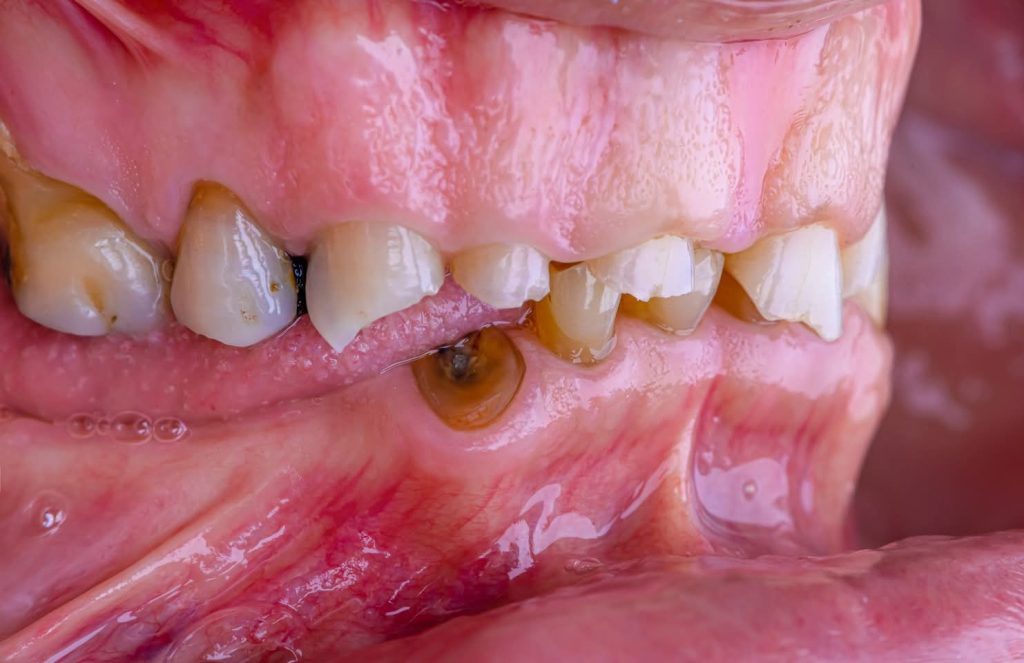

1. Diagnostic Phase:

This phase began with:

Extraoral examination: Included palpation of the masticatory muscles. The patient showed no signs of Temporomandibular Disorders (TMD).

Intraoral examination and determination of the vertical dimension at occlusion and rest using the phonetics method. This involved the physiologic rest position and interocclusal distance protocol, where the patient was instructed to say the labial “M” sound (e.g., in EMMA) without tensing the lips, allowing the mandible to settle in the rest position.

Fortunately, the patient was classified as Category I according to Turner and Missirlian’s (1984) classification, with an interocclusal space exceeding 5 mm.

2. Corrective Phase:

This phase included all necessary corrective procedures:

Extraction of hopeless teeth.